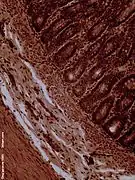

Transmission electron microscope (TEM) image of human jejunum

The interior surface of the jejunum—which is exposed to ingested food—is covered in finger–like projections of mucosa, called villi, which increase the surface area of tissue available to absorb nutrients from ingested foodstuffs. The epithelial cells which line these villi have microvilli. The transport of nutrients across epithelial cells through the jejunum and ileum includes the passive transport of sugar fructose and the active transport of amino acids, small peptides, vitamins, and most glucose. The villi in the jejunum are much longer than in the duodenum or ileum.

- The villi of the jejunum look like long, finger-like projections, and are a histologically identifiable structure.